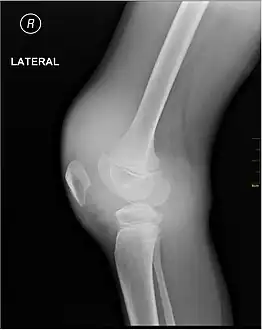

X-ray of Hemarthrosis